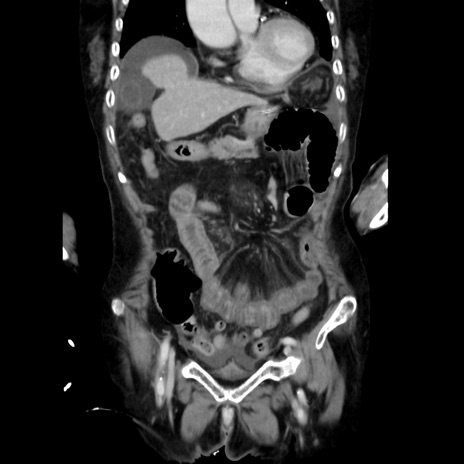

症例40(冠状断像)

【症例】90歳代女性

【主訴】腹痛・嘔吐

【現病歴】 食欲低下、嘔吐があり昨日他院受診。肺炎と診断され入院となる。入院後より腹部全体に圧痛あり。胃管留置され経過みていたが、症状持続するため、

当院転院となる。

【既往歴】胸椎圧迫骨折、胆石症

【身体所見】腹部:中央に激痛あり、圧痛あり、反跳痛不明

【データ】WBC 17100、CRP 18.82

冠状断像